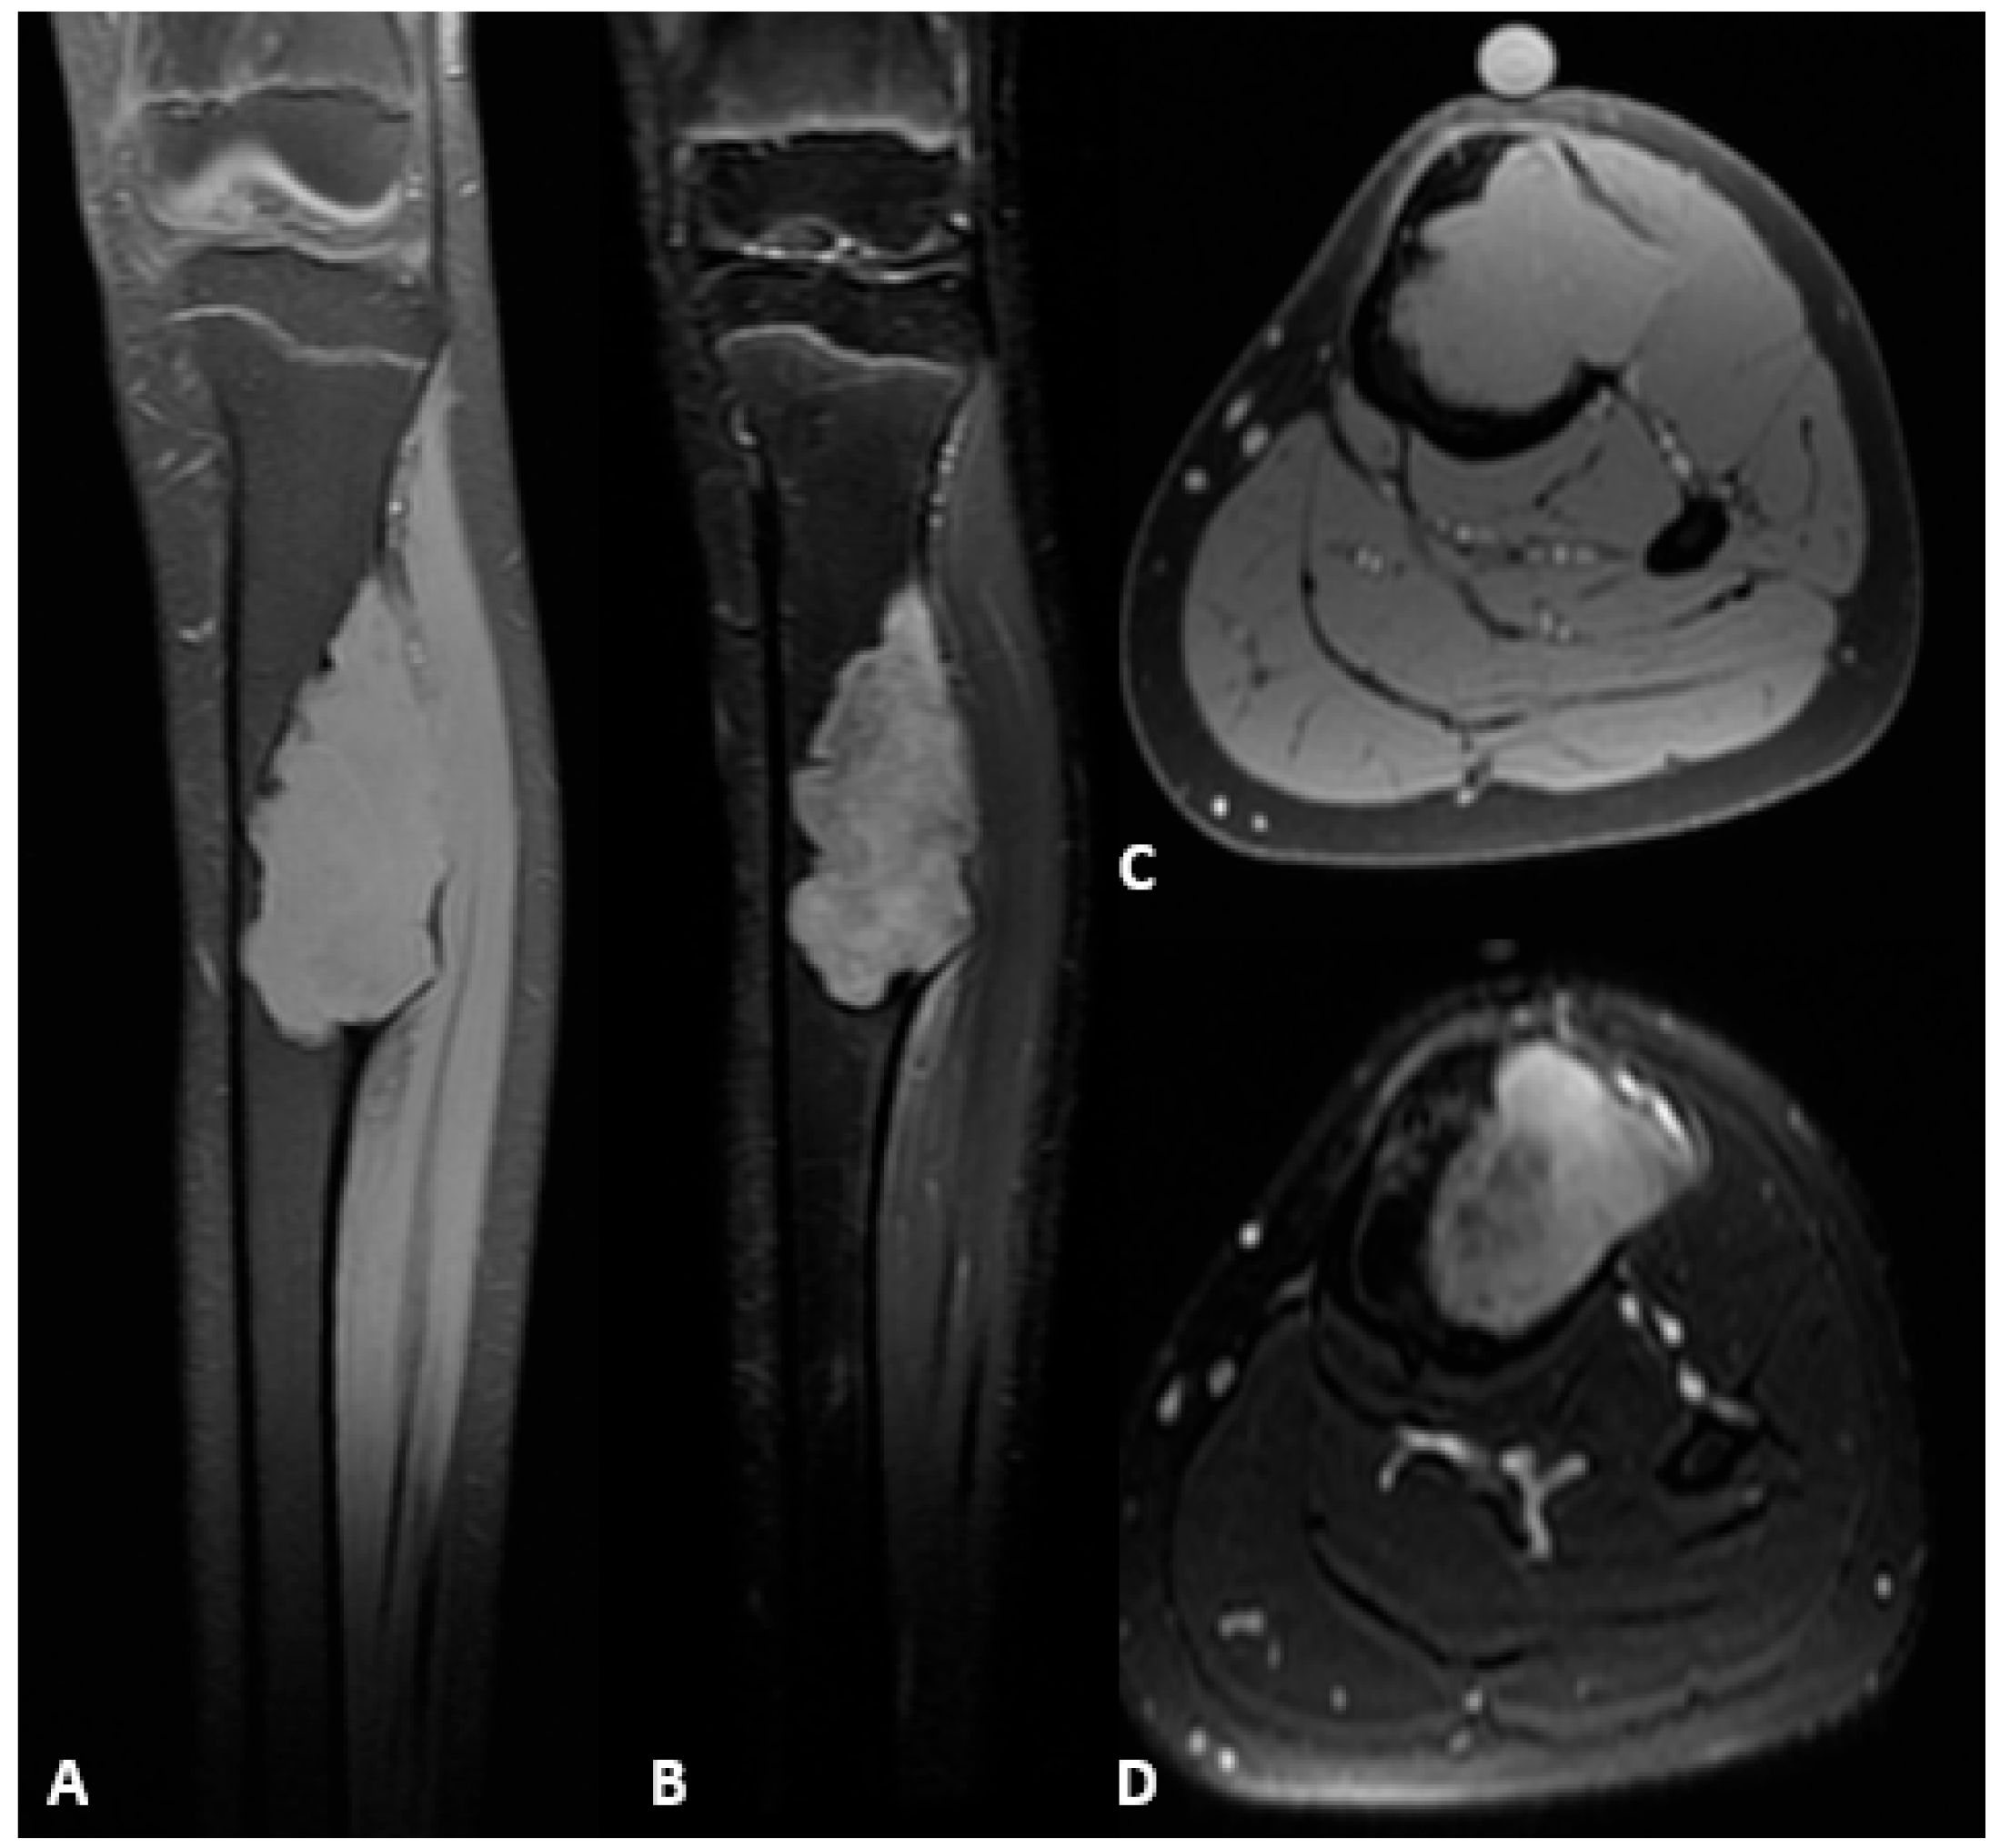

Figure 1.

Preoperative radiographs showing an osteofibrous dysplasia-like adamantinoma (OFD/LA) in the left tibial diaphysis. (A) Anteroposterior view. (B) Lateral view.

Figure 2.

Preoperative MRI of the left tibial diaphysis demonstrating an OFD/LA. (A) Hypointense lesion on T1-weighted sequence, coronal plane. (B) Hyperintense lesion on T2-weighted fat-suppressed sequence, coronal plane. (C) Hypointense lesion on T1-weighted sequence, axial plane. (D) Hypointense lesion on T2-weighted sequence, axial plane.